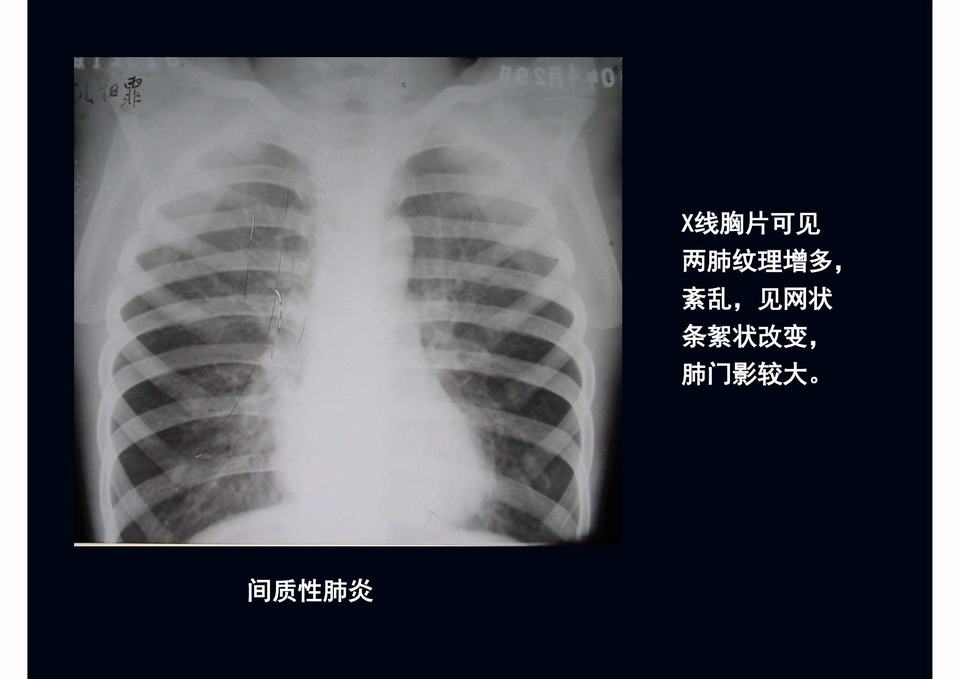

图04